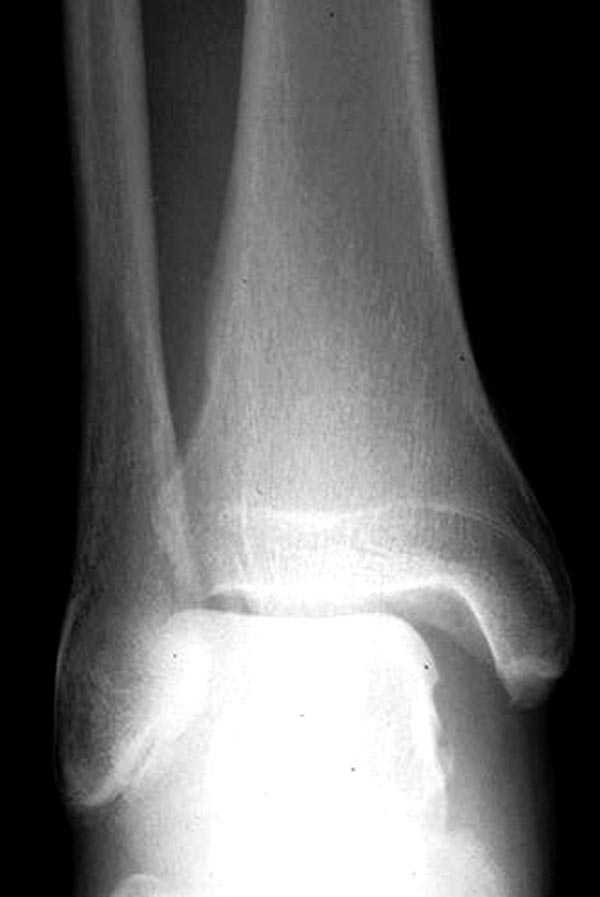

Здесь как раз тот случай, когда рентгеновский снимок скрывает главную проблему. "Ходит, прихрамывая на правую ногу, отмечает боли в правом голеностопном суставе" По описанию клиника типичная для повреждения голонестопного сустава - синдесмоза.

При проксимальных переломах малоберцовой автоматически необходимо подозревать повреждение синдесмоза - Maisonneuve Fracture.

На прямой проекции можно увидеть расширенную медиальную щель, и на мортизе укорочение малоберцовой.

Невозможно устранить проблему фиксацией малоберцовой пластиной или другими методами, потому что главная проблема - разрыв межберцовой мембраны, которая находится между костями и внизу в голеностопе в синдесмозе.